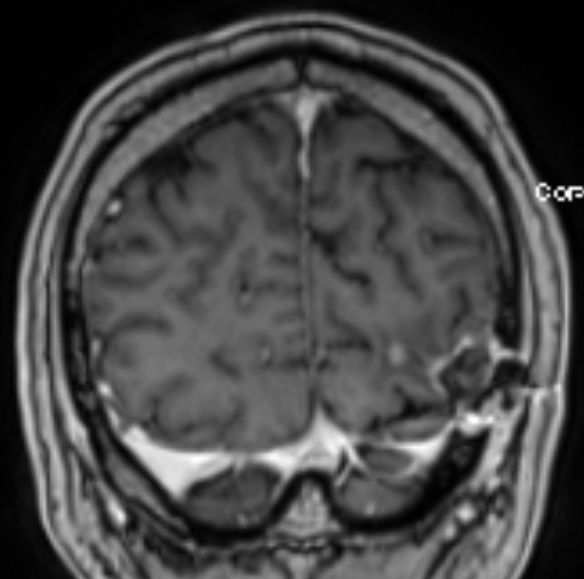

• 54-jähriger Mann, der vor 4 Jahren ein Adenokarzinom des rechten Lungenoberlappens cT4 cN1 M0 entwickelte

•  Cisplatin / Alimta - Chemotherapie, dann Radio –Chemotherapie 50Gy, 3 Zyklen simultan Cisplatin und Pemetrexed

• extrapleurale Oberlappenresektion,  Lymphadenektomie

• postoperatives Stadium ypT3 ypN0 L0 V0 G3

• adjuvante Bestrahlung der Thoraxwand rechts ED 3 Gy, GD 30 Gy

• vor 2 Jahren Metastase links parieto – occipital,  neurochirurgische Entfernung, Bestrahlung des Neurokraniums mit 30 Gy, ED 3 Gy

• vor 1 Jahr  Exstirpation einer Hirnmetaste links occipital, Bestrahlung des Hirnmetastasenbettes links occipital mit 40 Gy, ED 2 Gy

Die linke Spalte zeigt MRTs vor 7 Monaten, die rechte Spalte aktuelle MRTs.

Die MRTs zeigen eine Zunahme der Gadolinium-anreichernden Bezirke. Die Exzision erbrachte Großhirngewebe mit Anteilen einer Nekrose. Kein Tumorgewebe.